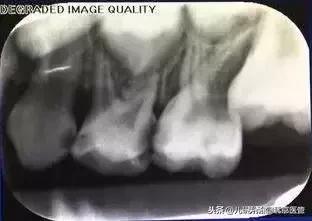

左上六龄齿萌出阻生且破坏第二乳磨牙

六龄齿牙冠卡在最后一颗乳磨牙的牙冠下方,不光让磨牙咬关系出现异常,还非常容易造成卡住的牙冠难于清洁,造成龋坏。所以,出现这样的情况一定能要及时就医,修正异常的位置排列,解决双重隐患。